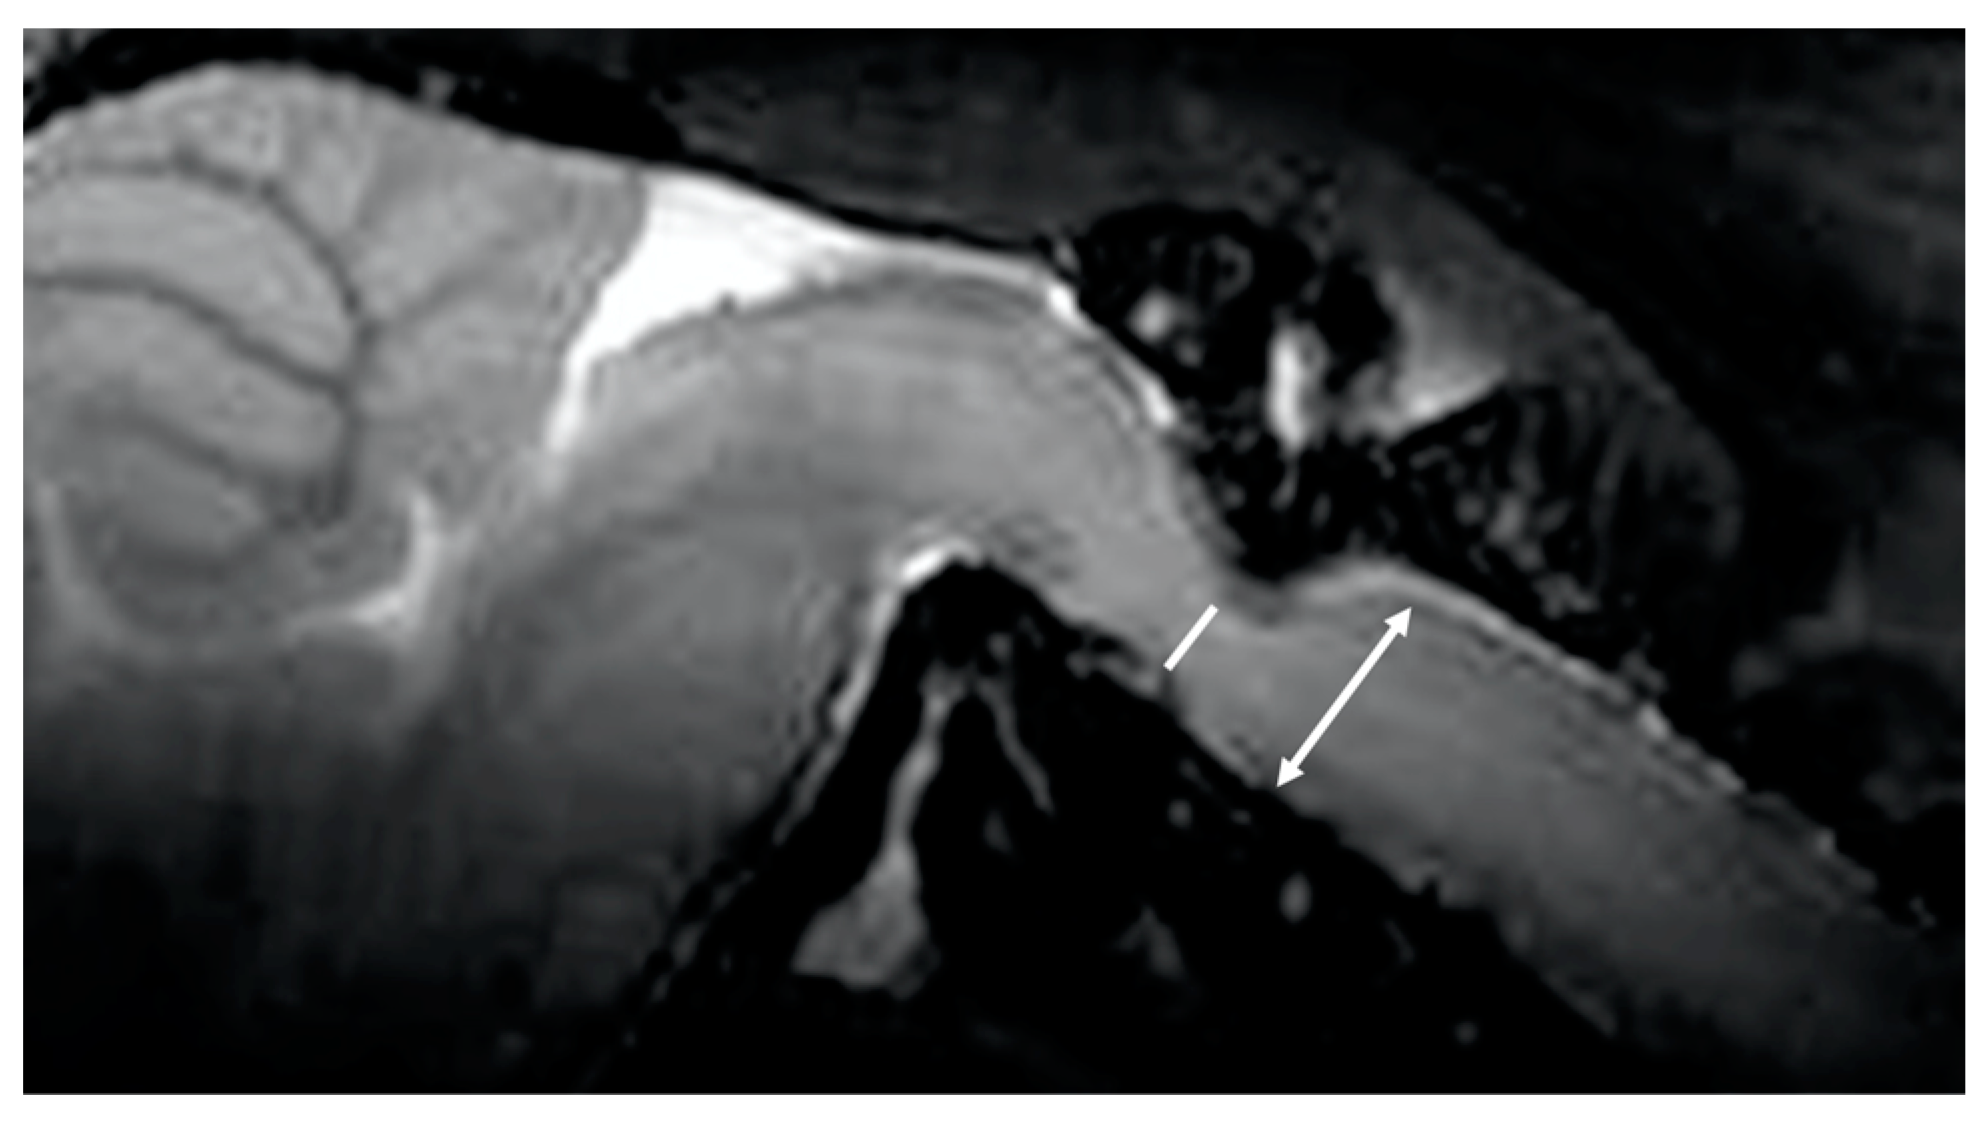

Two board-certified physicians and one senior author who specialized in the imaging of the CNS in laboratory animals independently measured the images of 30 mice (10 wild-type and 20 twy/twy mice) taken with the Time-SLIP technique 3 times. The examiners were blinded to the genotype of the mice. We defined the stir distance as the distance of CSF stirring in the sagittal plane within a single time period (3 s) in the fourth ventricle, where there is relatively more space, and three examiners took measurements 3 times for each mouse (Figure 2). Furthermore, the examiners also measured the antero-posterior diameter of the spinal cord and spinal canal on the MRI sagittal plane and calculated the canal stenosis ratio (CSR). (Figure 3) We examined the correlation between stir distance and CSR using Pearson’s correlation coefficient. Additionally, to eliminate the potential impact of respiration on the dynamics of CSF, the respiratory rates of wild-type and twy/twy mice were recorded and compared.

Figure 3. Canal stenosis ratio. Canal stenosis ratio = 100 − (antero-posterior diameter of spinal cord) [White line]/antero-posterior diameter of spinal canal [two-headed arrow] × 100.